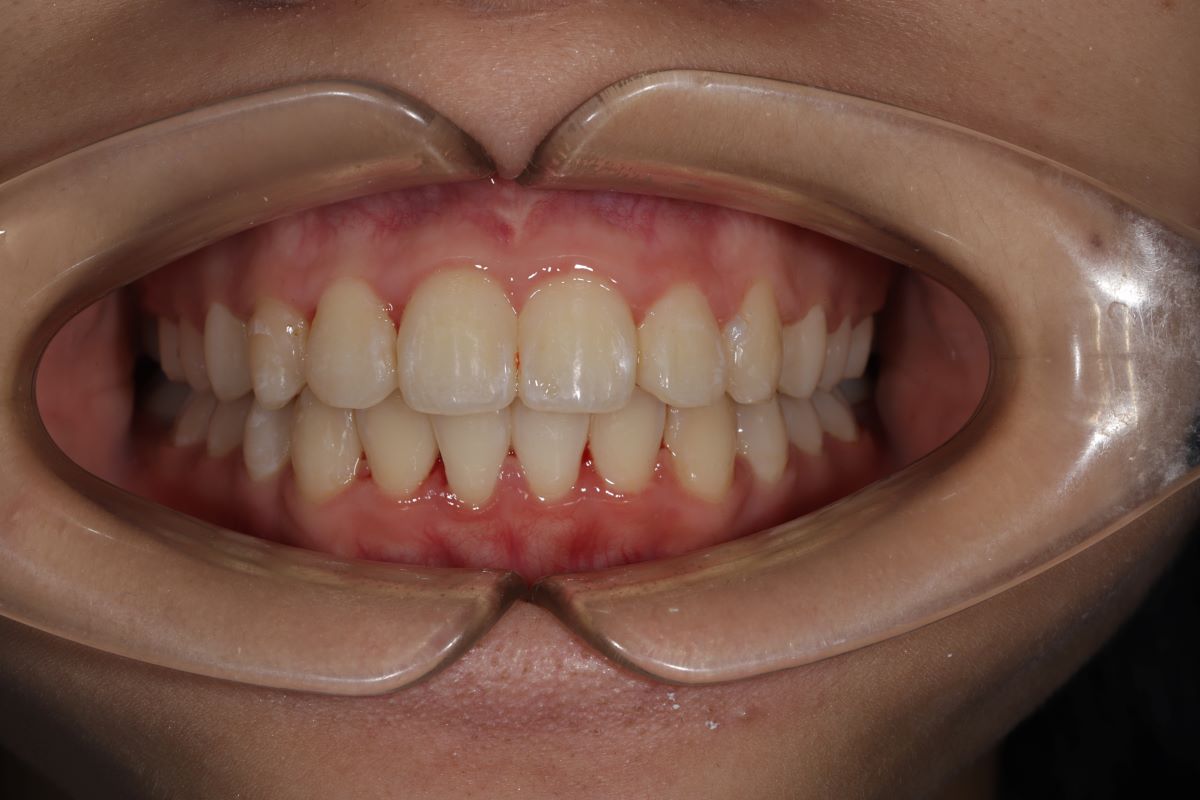

Kết quả sau niềng - Màn "lột xác" ấn tượng

- Sau khi tháo niềng, Diệp Anh thay đổi rõ rệt:

- Răng thẳng hàng, không còn chen chúc

- Khớp cắn chuẩn – ăn nhai tự nhiên

- Khuôn mặt cân đối, góc nghiêng hài hòa hơn

- Nụ cười rạng rỡ – tự tin trong giao tiếp, chụp ảnh